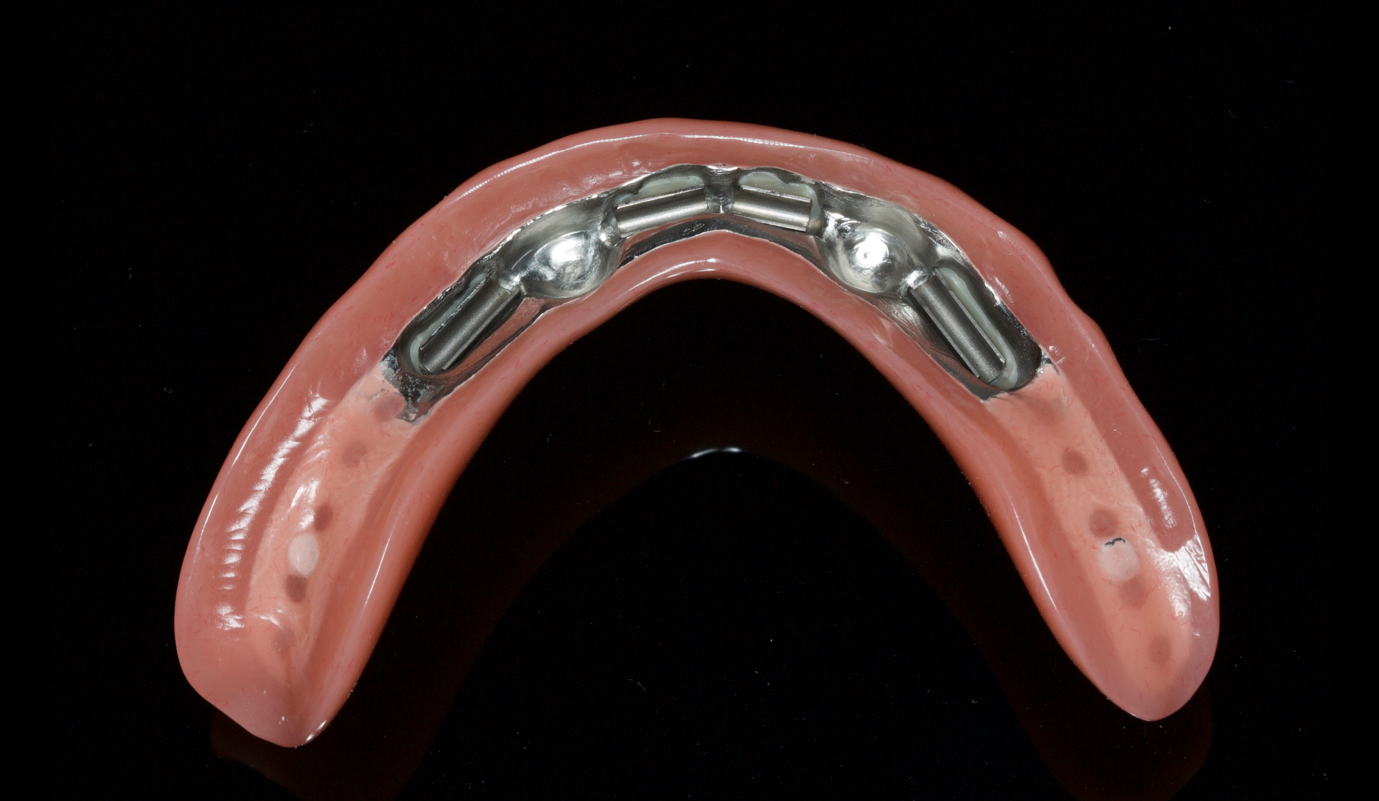

Exemplos em fase laboratorial

Casos de próteses sobre implantes